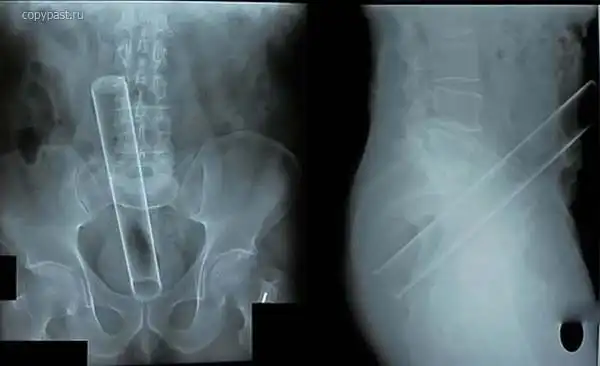

Пациент со стеклянной цилиндрической мензуркой в анусе. На уроках химии такого

не проходили

Стопка для шотов. В анусе. Зачем ее туда засунули? ))

Огромный вибратор в заднице. Залез полностью. Без хирургического вмешательства

достать не смогли. Больные люди...